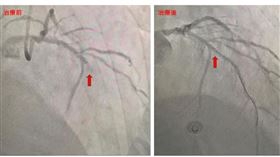

7旬翁嗆咳暈厥 1次竟2大魔王上身

新竹一名76歲的老翁日前在工作時嗆咳,沒想到咳完後突...